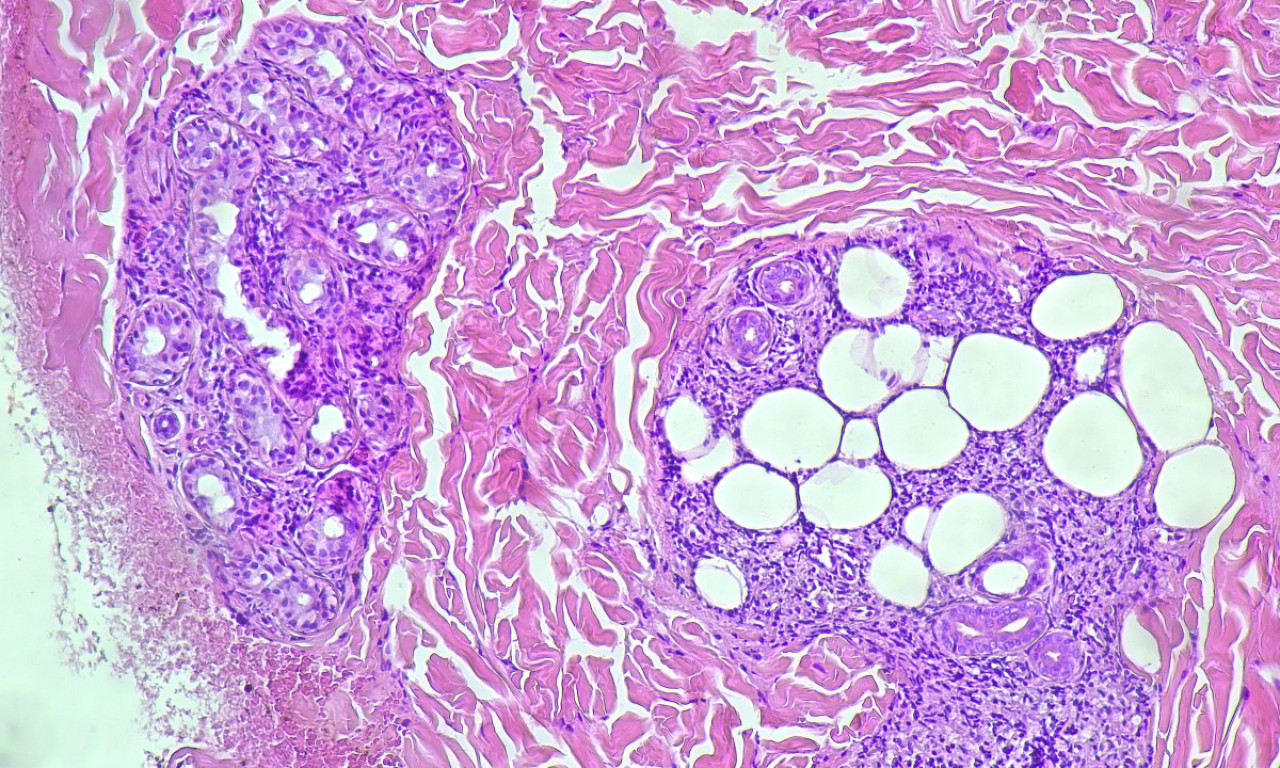

Lepra, poznata i kao guba, hronična je zarazna bolest koju izaziva bakterija Mycobacterium leprae.

Najčešće zahvata kožu, periferne nerve, sluzokožu gornjih disajnih puteva i oči.